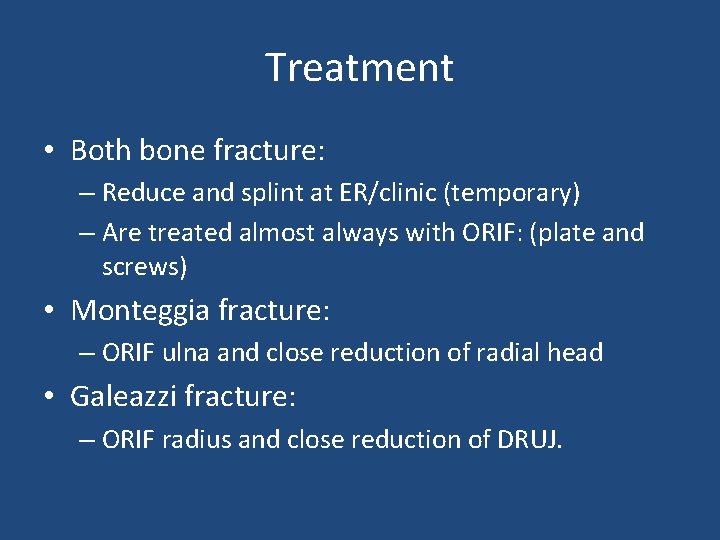

Treatment • Both bone fracture: – Reduce and splint at ER/clinic (temporary) – Are treated almost always with ORIF: (plate and screws) • Monteggia fracture: – ORIF ulna and close reduction of radial head • Galeazzi fracture: – ORIF radius and close reduction of DRUJ.